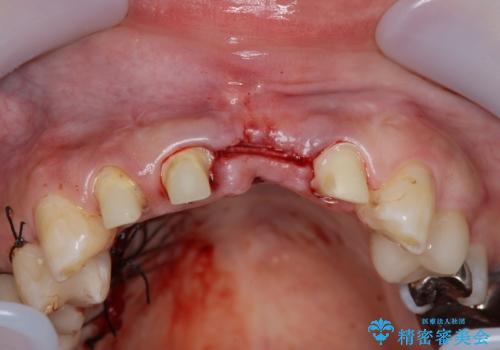

不良インプラントを除去し最終的にブリッジによる補綴で審美性の改善を行うこと、その準備として骨の造成・歯肉の移植による歯の欠損部顎堤のボリュームを維持・増大を計画します。

感染したインプラントからは排膿が間欠的に認められ、掻爬・除去が検討されうるような状況でした。

より審美的な改善を強く求められたため、インプラントを除去し可及的に欠損部顎堤を増大したのちブリッジによる審美改善を行いました。